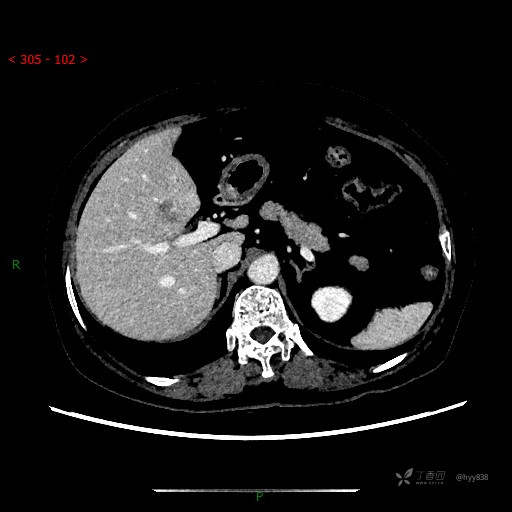

增强动脉期